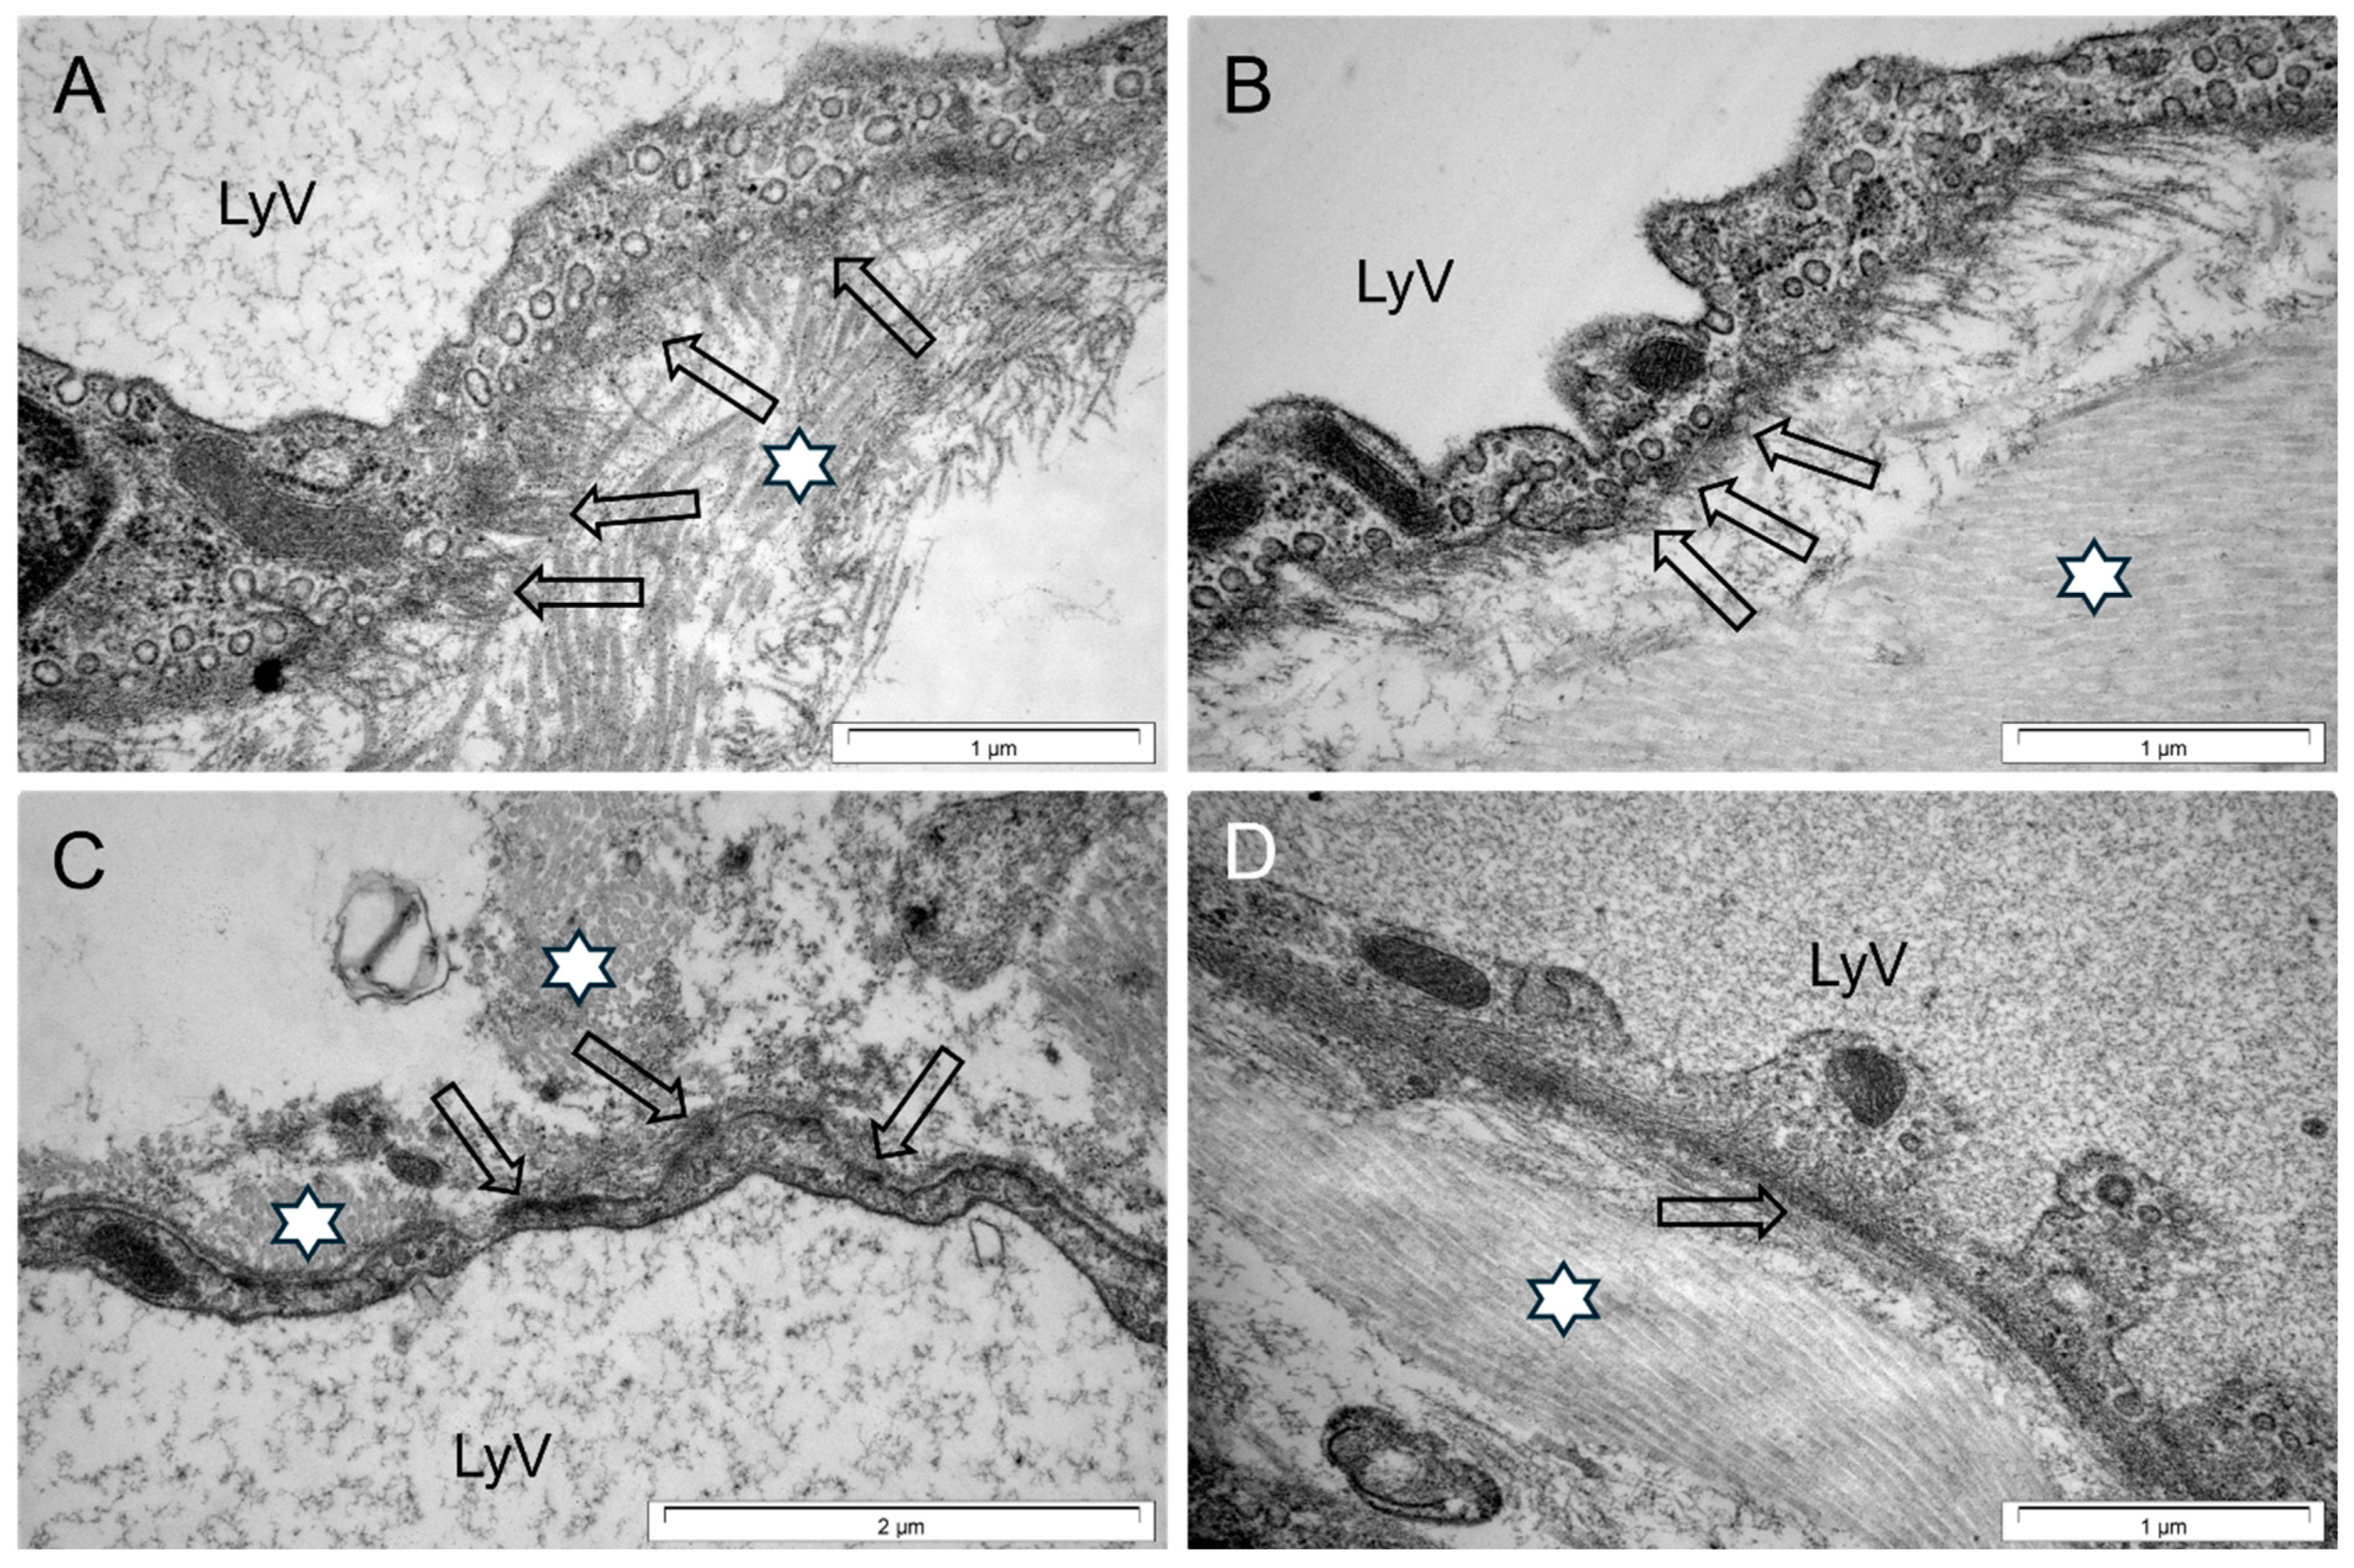

2.7. Ultrastructure and Morphometric Analysis

3.3. Cardiac LyV Density and Structural Remodeling

4.4. LyV Remodeling Is Part of Cardiac Remodeling